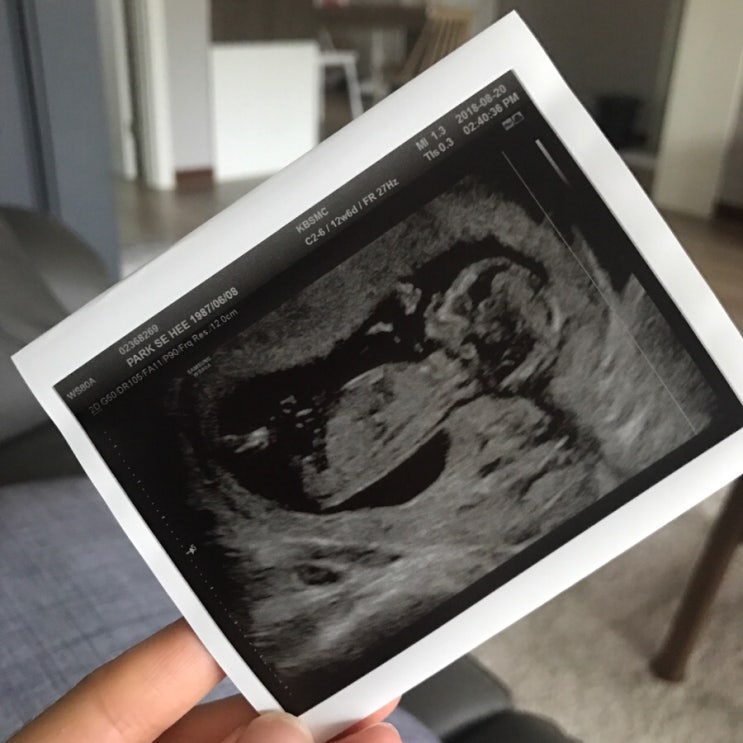

라니일기:) 11주부터 14주까지의 기록

라니일기11주부터 14주까지의기록 라니는 무럭무럭 자라서11주가 되었다 :) 딸기만하다는 라니... *&n...